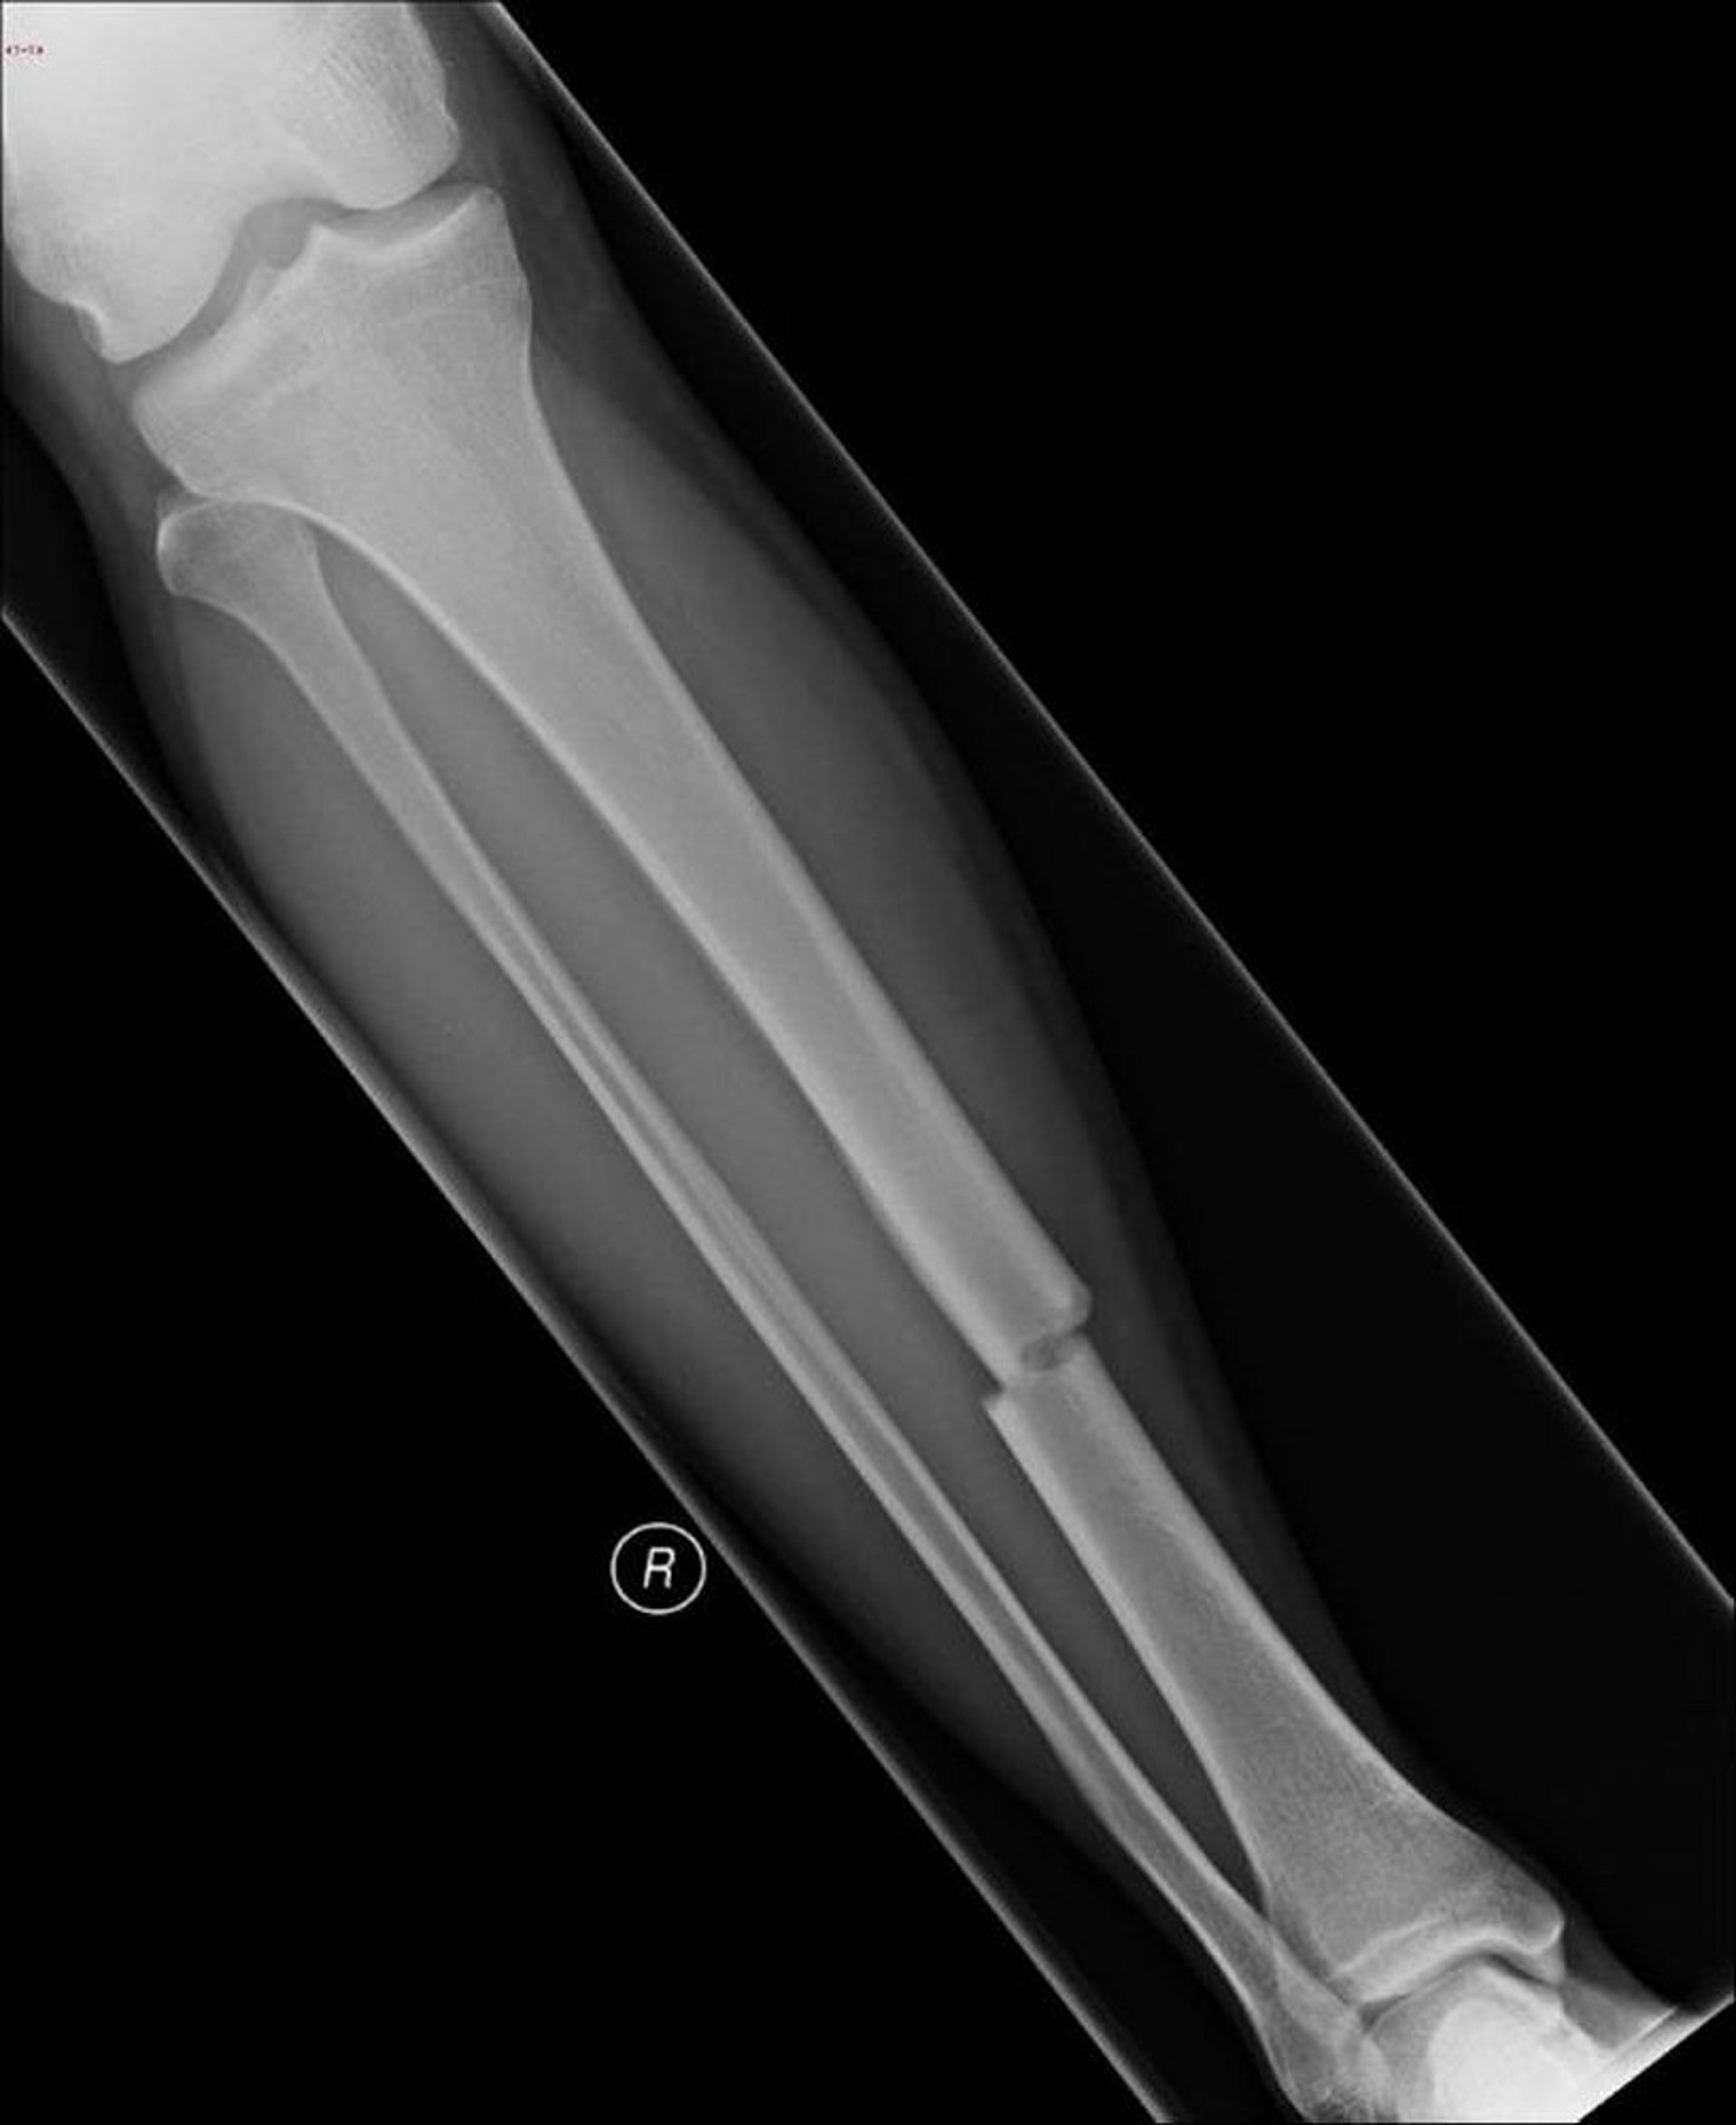

Fracture du tibia

Cette radiographie montre une fracture au milieu du tibia.

Image publiée avec l’aimable autorisation de la Dre Danielle Campagne.